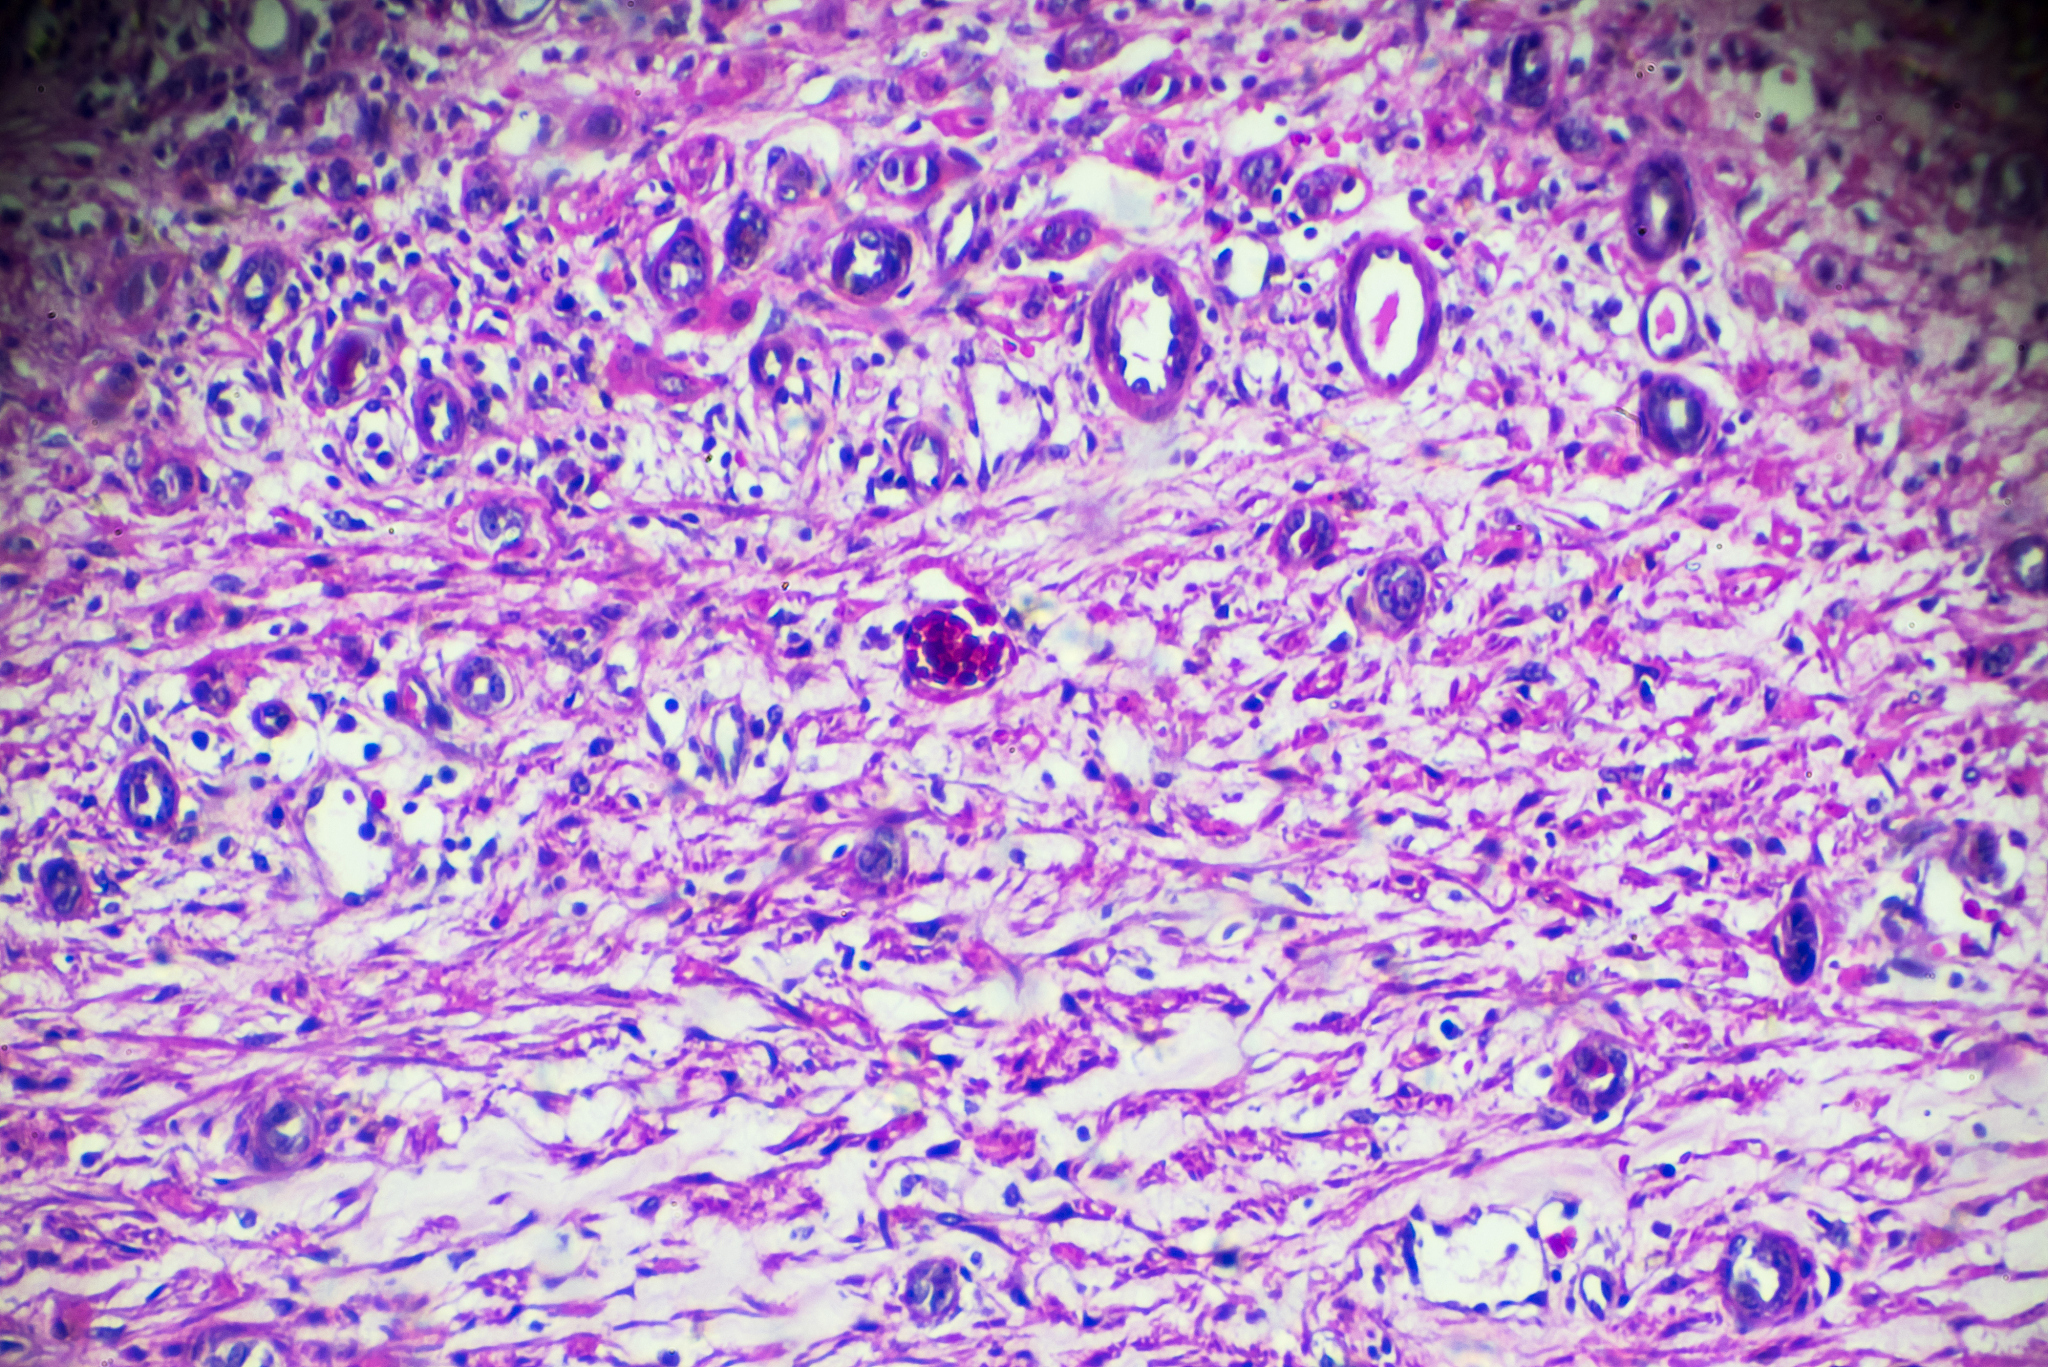

膜性肾病(Membranous Nephropathy)是一种以肾小球基底膜增厚和免疫复合物沉积为特征的肾小球疾病。以下是膜性肾病当前的一些研究趋势: